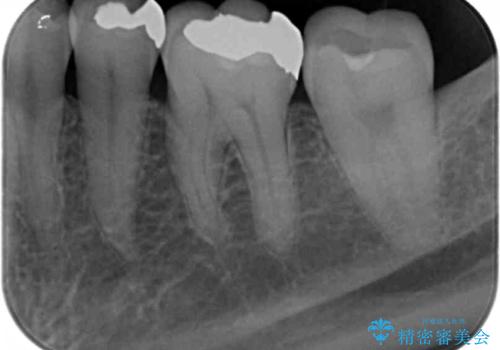

銀歯を丁寧に除去し、セラミクインレーによる置き換えを行いました。

セラミックインレーの治療に際しては、拡大鏡を用いた丁寧な除去・形成、シリコン印象材による精密な型取りを行い、虫歯の再発を防ぐような精密修復を実践していきます。